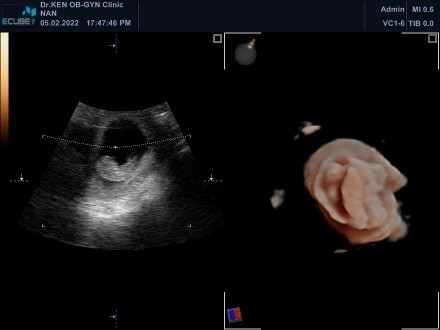

ซาวทั้ง 2 และ 4 มิติเลยค่ะ